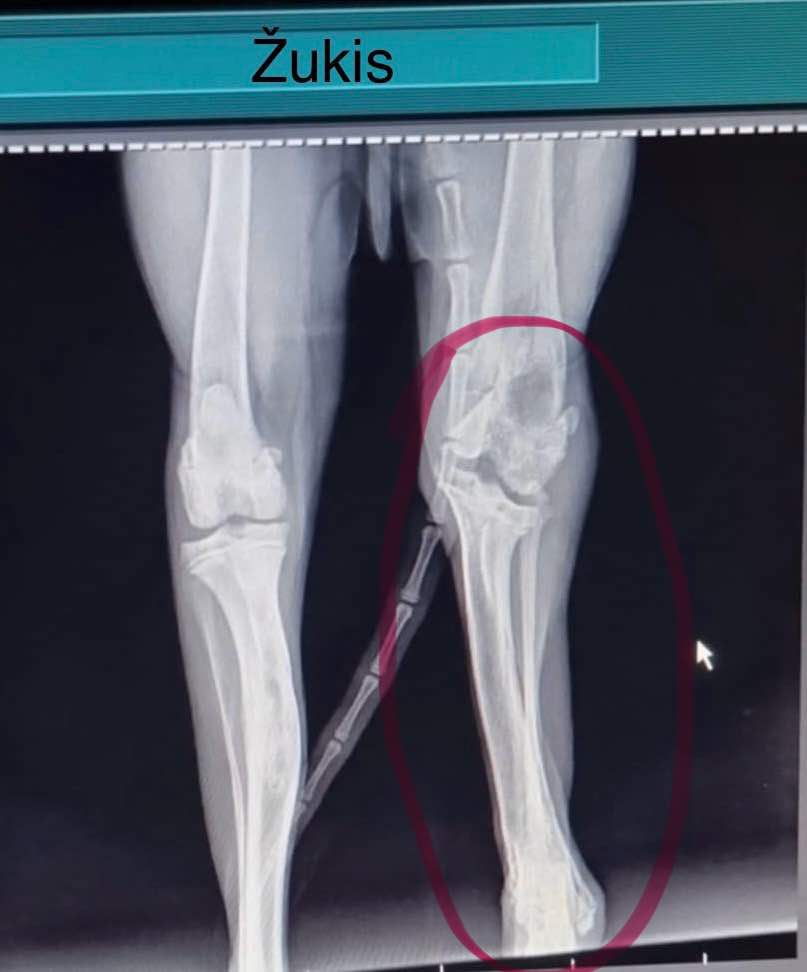

Tulin tarhalle, koska en enää ollut tarpeellinen omistajilleni, mutta täällä minä olen – ystävällinen, rakastettava ja elämäniloinen! Olen nuori ja suloinen koira, mutta elämässäni on ollut omat haasteensa. Aluksi täällä tarhalla olin rauhallinen (ja stressaantunut), mutta kun aloin leikkiä muiden koirien kanssa ja elämä kävi aktiivisemmaksi huomasin, että takajalkani alkoi ontua. Minut kuvattiin röntgenissä ja paljastui, että jaloissani on murtumia, jotka eivät parantuneet kunnolla. Jalkani ovat niiden jäljiltä jääneet epämuodostuneiksi. Ehkä olin joskus joutunut auton alle, mutta kukaan ei hoitanut vammaani silloin – en ole ihan varma.